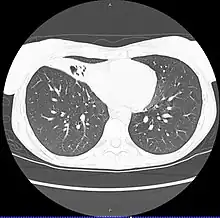

| CT scan of patient with right middle lobe aspiration and Mycobacterium avium infection. | |

MAC usually affects patients with abnormal lungs or bronchi. However, Jerome Reich and Richard Johnson describe a series of six patients with MAC infection of the right middle lobe or lingula who did not have any predisposing lung disorders.[17][18]

The right middle lobe and lingula of the lungs are served by bronchi that are oriented downward when a person is in the upright position. As a result, these areas of the lung may be more dependent upon vigorous voluntary expectoration (cough) for clearance of bacteria and secretions.

Since the six patients in their retrospective case series were older females, Reich and Johnson proposed that patients without a vigorous cough may develop right middle lobe or left lingular infection with MAC. They proposed this syndrome be named Lady Windermere syndrome, after the character Lady Windermere in Oscar Wilde's play Lady Windermere's Fan. However, little research has confirmed this speculative cause.[19]

- Chest X-ray or CT scan showing evidence of right middle lobe (or left lingular lobe) lung infection